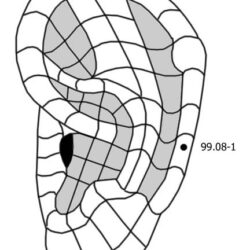

הסבר והדגמה של קריסטל המים 66.13 Shui jing

קריסטל המים 66.13 Shui jing היא נקודה חשובה באקופונקטורה של מאסטר טונג לטיפול בהפרעות גינקולוגיות, בוידאו אני מסביר אודות הנקודה ומדגים את בדרך לאתר ולדיקור.

הסבר והדגמה של קריסטל המים 66.13 Shui jing קרא עוד »